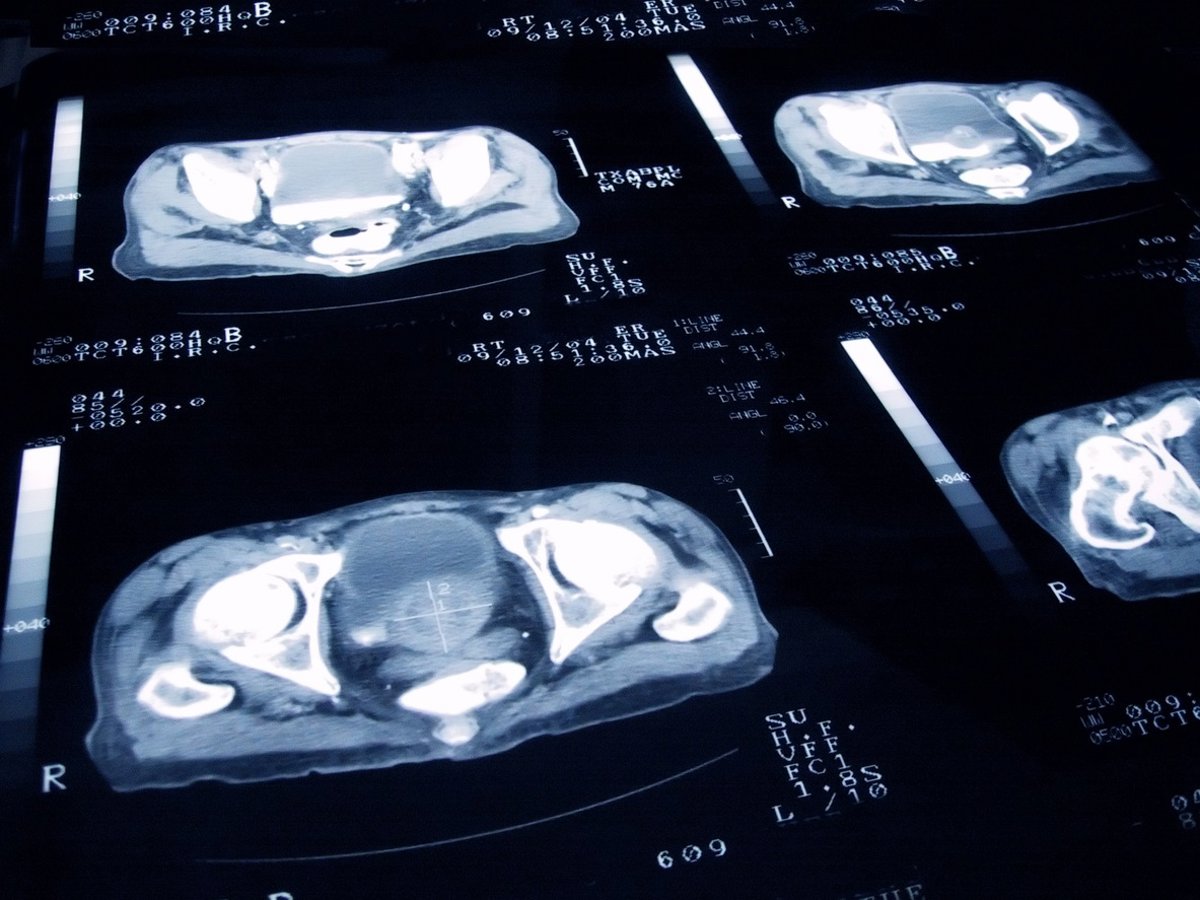

Archivo - Cáncer de próstata.

Archivo - Cáncer de próstata. - JAMESBENET/ ISTOCK - Archivo